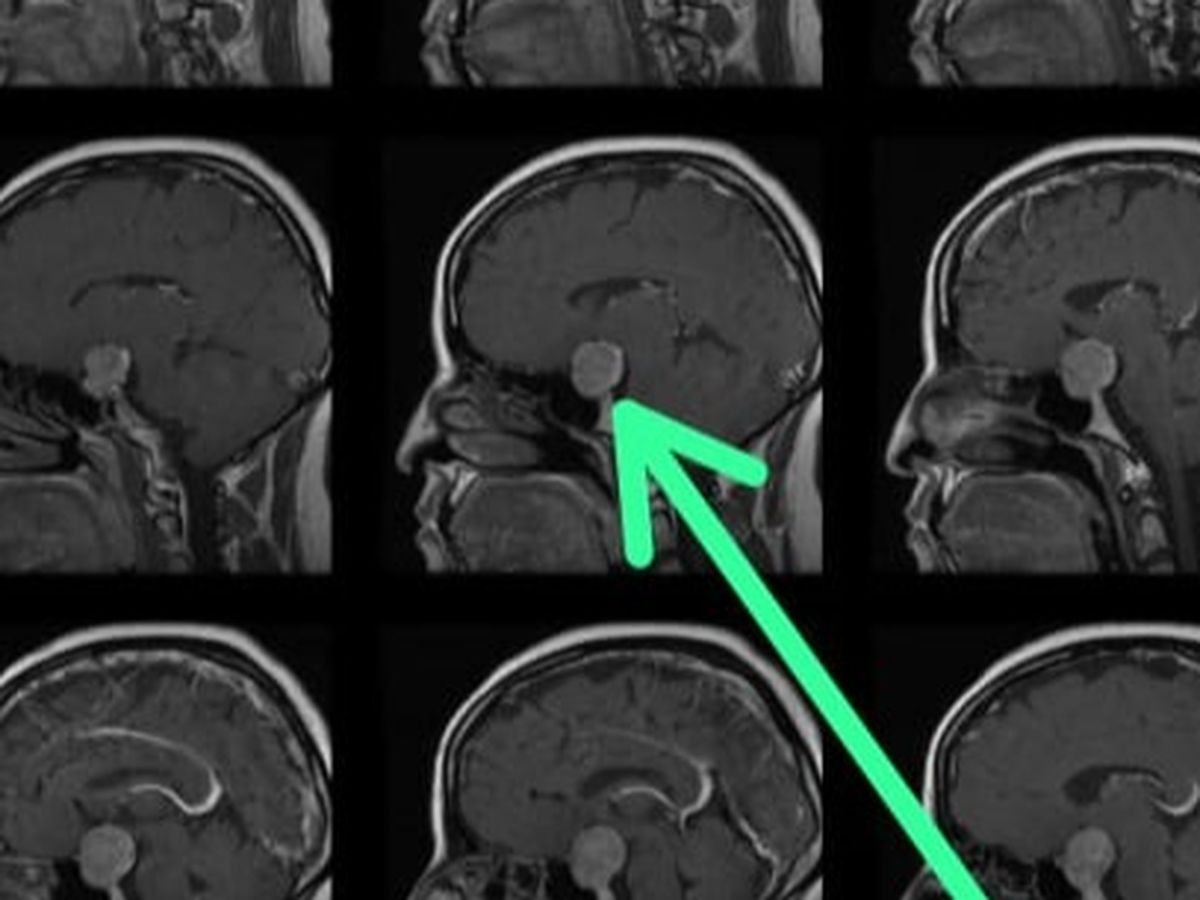

Recientemente, me diagnosticaron un tumor cerebral (macroadenoma en la hipófisis), se ha determinado que necesito una operación urgente para tratar esta condición. Esta noticia ha sido un desafío enorme para mí y mi familia, pero estamos determinados a enfrentarla con valentía y optimismo.